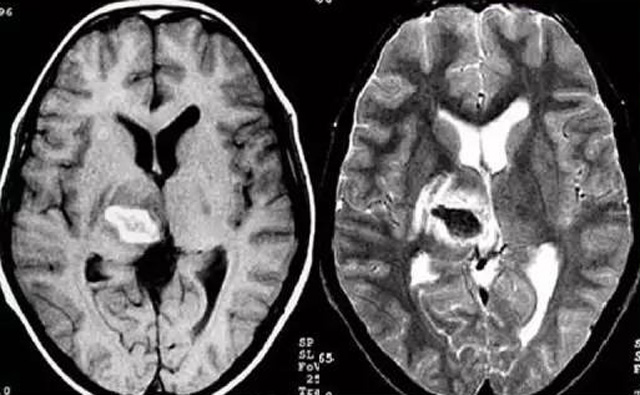

經(jīng)顱多普勒超聲(TCD)磁共振MRI檢查腦出血診斷的作用是什么?

發(fā)現(xiàn)病人出血腦梗相關(guān)癥狀時候第一時間就醫(yī),需要攜帶以往的影像檢查資料。向醫(yī)生提供相關(guān)的病史基本資料。做影像檢查時候需要全身不攜帶金屬物品。檢查時候身體保持不動,不然偽影對檢查結(jié)果有干擾。磁共振MRI發(fā)現(xiàn)缺血性卒中后,幫助進(jìn)一步查找病因。由于CT上小腦跟腦干顱骨影響,容易導(dǎo)致漏診。MRI檢查可以對CT檢查不足的補充。短暫的腦缺血TIA也需要進(jìn)行影像檢查。短暫性缺血一般10幾分鐘后好轉(zhuǎn)。檢查目的可以確定TIA的病因。降低腦梗死的發(fā)生率。磁共振有助于排出TIA表現(xiàn)的顱內(nèi)病變,有診斷及時治療的價值。磁共振MRI檢查時間比較長,不太適合急診病人。但是可以發(fā)現(xiàn)腦干小腦的出血問題。因為急性腦梗死的早期和急性期,缺血區(qū)的腦組織還沒有完全壞死,頭顱CT不能顯示病灶,所以就需要MRI磁共振檢查,這個對陳舊跟亞急性出血顯示比較好。缺點性價比不高,費用比較貴。頭顱的磁共振MRI在發(fā)病后的幾天CT的敏感降低時候發(fā)揮大作用。,MRI可作為診斷蛛網(wǎng)膜下腔出血和了解破裂動脈瘤部位的一種重要方法,必要時進(jìn)一步進(jìn)行DSA檢查,幫助制訂臨床的手術(shù)治療方案,

經(jīng)顱多普勒超聲(TCD)有效沒有創(chuàng)傷性的檢查方法,是檢查腦血管的設(shè)備之一,它目前廣泛應(yīng)用于臨床,檢查判斷腦出血卒中的頭顱里面的內(nèi)動脈外動脈的病變問題。診斷顱內(nèi)動脈狹窄或閉塞性病變。顱外頸部動脈狹窄或閉塞性病變,評價顱外動脈嚴(yán)重狹窄或閉塞對顱內(nèi)血流速度的影響。頸動脈內(nèi)膜剝脫手術(shù)前預(yù)測夾閉作用、術(shù)后評估顱內(nèi)血流變化。